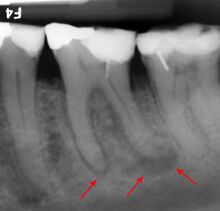

The inferior alveolar nerve (IAN), a branch of the trigeminal nerve (cranial nerve V), is a nerve that runs through the mandible (lower jaw) and supplies sensation to all the lower teeth, the lip and the chin. The lower teeth, and in particular the lower wisdom teeth, can therefore be in close proximity to this nerve. Damage to the inferior alveolar nerve is a risk of lower wisdom tooth removal (and other surgical procedures in the mandible).[16] This means there is a risk of temporary or permanent numbness or altered sensation to the lip +/- chin on the side the surgery is taking place. Therefore, in order to assess this risk and inform the patient, the position of the inferior alveolar nerve in relation to a lower wisdom tooth needs to be assessed radiographically prior to extraction.[16]

The proximity of the root to the canal can be assessed radiographically and there are several factors which can indicate high risk of nerve damage:[17]

- Darkening of the tooth root where it crosses the canal[17]

- Deviation of the canal[17]

- Narrowing of the roots[17]

- Loss of the lamina dura of the canal[17]

- Juxta apical area: a radiolucency associated with the root of the tooth which is not caused by periapical infection[17]